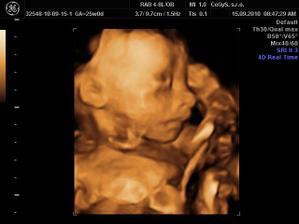

Náš anjelik🙂